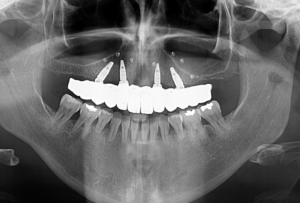

If you have not extracted your teeth (and they are indicated for extraction), you can do that in Queen clinic or in the country where you live. For the need of all on 6 or all on 4 dental implants placement we should do the three-dimensional (CBCT) x rays and temporary denture. These are the first steps.

Did you know that all on 6 and all on four dental implants treatments are planned backwards? That`s right, first the entire prosthetic part is planned, i.e. where the teeth will be in relation to the lip and where the gums will be, whether you will be able to speak clearly with the new teeth, whether they will be a suitable support for the lip and similar details.

If you are in Belgrade, we can easily move on because we have X-ray centers and x rays available, but also an indispensable clinical examination. At our scheduled appointment, we can already see all the details and provide you with a lot more information that will influence your decision about dental implants.

If you are not in Belgrade, of course contact us by phone or email, but if possible, send us cbct x ray.

Also, you can easily make those x rays a in Belgrade, at a price of around 70 euros for both jaws.

The first step is a dental examination by our team of specialists. Based on the examination and analysis of X-rays, our doctors will suggest and explain everything about the treatment.